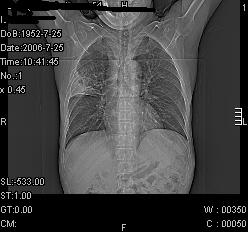

患者,男,54岁,咳嗦,咳痰20天。抗炎治疗2周。现esr76mm/h,目前患者症状明显好转,但发现两次ct片未见明显变化。两次分别做与7.25、7.31。第一次诊断右肺上叶炎症累计胸膜。大家看,从影像上内排除结核吗?

结核的可能性非常大,右上肺病变应该考虑干酪性肺炎。理由:

1.纵隔内多发淋巴结肿大。

2.esr76mm/h。

3.虽经抗炎治疗肺窗病灶有所吸收、减小,但纵隔窗病灶形态、密度、范围无明显变化。如果是单纯的大叶性肺炎,“抗炎治疗2周,目前患者症状明显好转”病灶应该基本消散了,至少也处于吸收消散期,密度变淡、范围变小。同时本病例所示其内的密度不均匀,见多发大小不一空洞样影也不符合大叶性肺炎吸收消散期表现。

病灶特点:片状 索条 结节混杂影,部分融合,密度不均,广泛累及相应胸膜.

临床治疗;二周未吸收.但症状好转.

多考虑:肺结核.